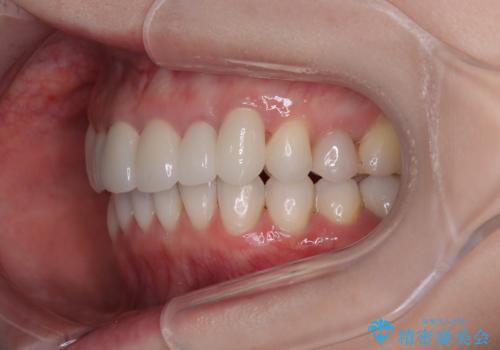

- 全体的なデコボコと、奥歯の欠損を放置した結果倒れ込んだ奥歯などを気にして来院された患者様です。

ワイヤー矯正の方が理想的な仕上がりとできる状態でしたが、上顎前歯にクラウンが装着されているため、インビザラインにて矯正治療を行うこととしました。

インビザラインのみで対応できないときにはワイヤー矯正を併用することとし、矯正治療後にはオールセラミッククラウンによる補綴治療を行うこととしました。

矯正治療自体はインビザラインで満足のいく仕上がりとなりました。

前歯は根管治療が必要となり、元々舌側に入り込んでいた左上2番目の歯は歯周外科処置により歯肉ラインを整えることとしました。

欠損部位は傾斜歯軸を起き上がらせることができたため、オールセラミッククブリッジにて補綴治療を行いました。

全顎的に満足のいく仕上がりとなりました。